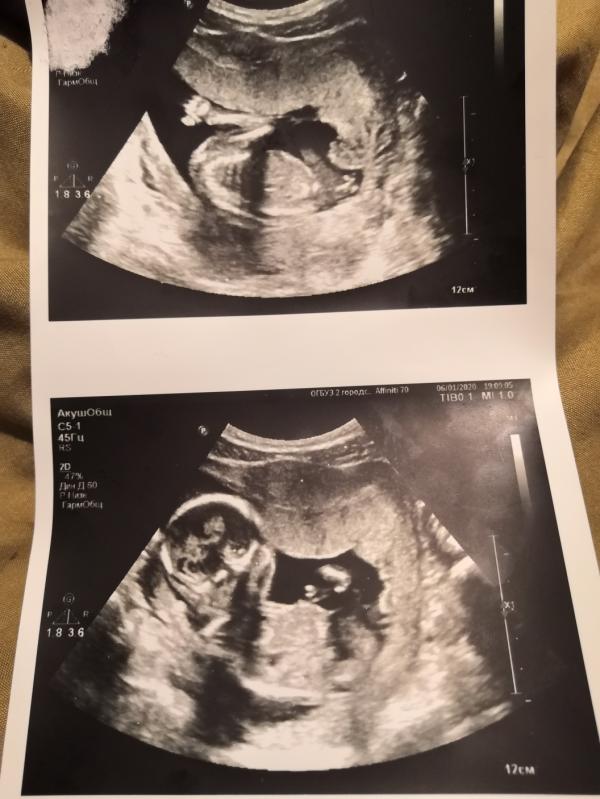

На узи сходили, ручкой и ножкой нам помахал, попу и не только показали😍

Ну малыш наш точно в папу, личико хмурит, позирует, ещё и мальчик... В 16.4 недели поставили срок 17 недель и сказали считать именно как 17,а не меньше 🤔

Для тех, кому как и мне все это интересно, прилагаю фото живота и узи, все сделано в один день)